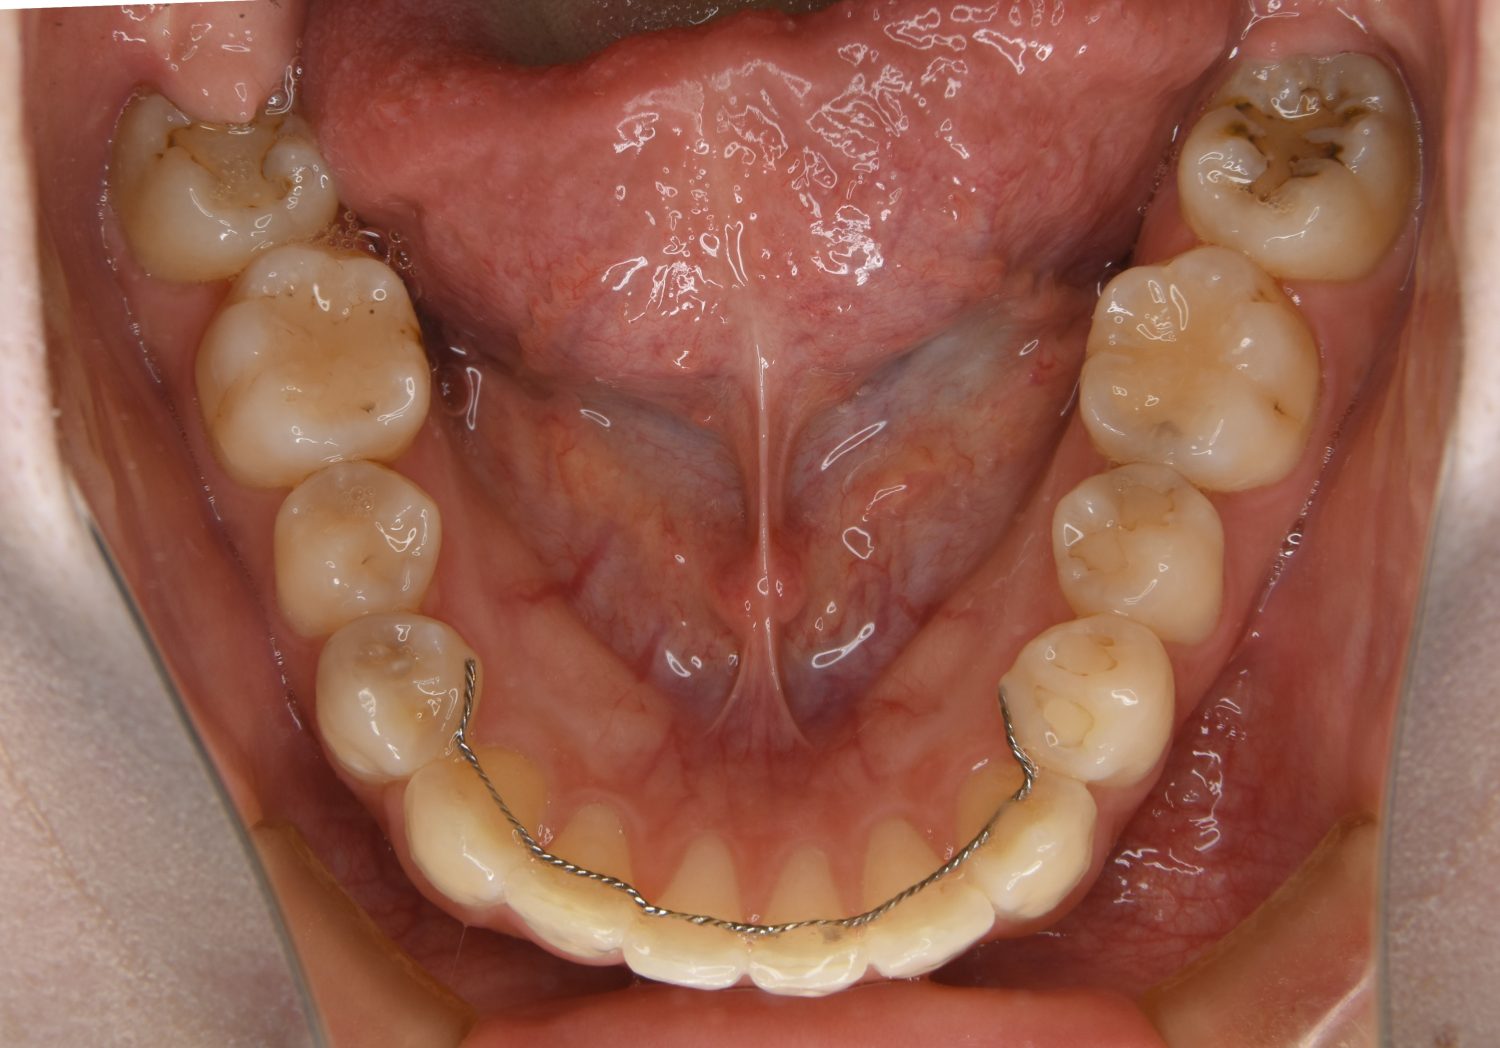

前歯部開咬の症例紹介②

Before

主訴

前歯で物が噛めない

治療内容

上下ラビアルブラケット(唇側装置)に矯正用アンカースクリューを併用し非抜歯で治療を行いました。

上下の前歯が開いており前歯では全く噛めていない状態でした。臼歯の圧下を行うことで機能面のみでなく審美面も改善しました。